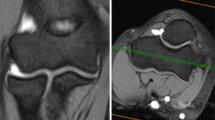

Angle measurement locations. Anatomical landmarks for definition of measurement locations are marked by white arrows in the axial view (A). Sagittal plane positioning (blue line) as applied for the angle measurement is shown for each measurement location (1–4) in the axial view with the corresponding location in the coronal view (B). Angle measurements are conducted in the sagittal view (C) in relation to the longitudinal humerus shaft axis (coronal plane: yellow line) which is depicted for each measurement location (1–4). Red line: axial plane (color figure online)

Angle measurement. At first, the volar (v) and dorsal (d) transmission from a convex to a lineal or concave surface of the spherical joint component was determined (white arrow) (A) and is shown for each measurement location in the sagittal view (1–4). For measurement (B) the transmission points are connected (blue line) and a circle (orange circle) is inserted that matches the surface of the spherical joint component. The angle (*) is measured between the longitudinal shaft axis (yellow line) and a line (green line) that connects the middle of the circle and the transmission point connecting line (blue line). Here, measurement location 3 (the volar part of the trochlea groove) was used for demonstration with an angle of 166°. These images are segments of the images depicted in Fig. 1C. For a wider depiction of these images, see Fig. 1C (measurement locations 1–4) (color figure online)